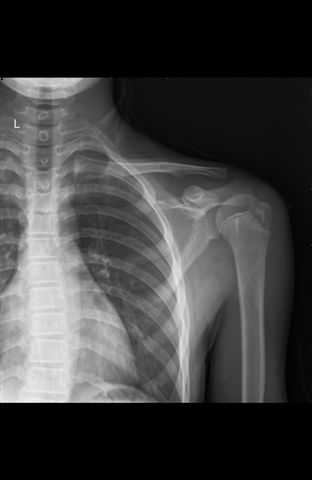

当天对侧对比:

第一次诊断为骨折是正确的,看左侧对比,右肱骨上段内侧的骨质有轻微凹陷。